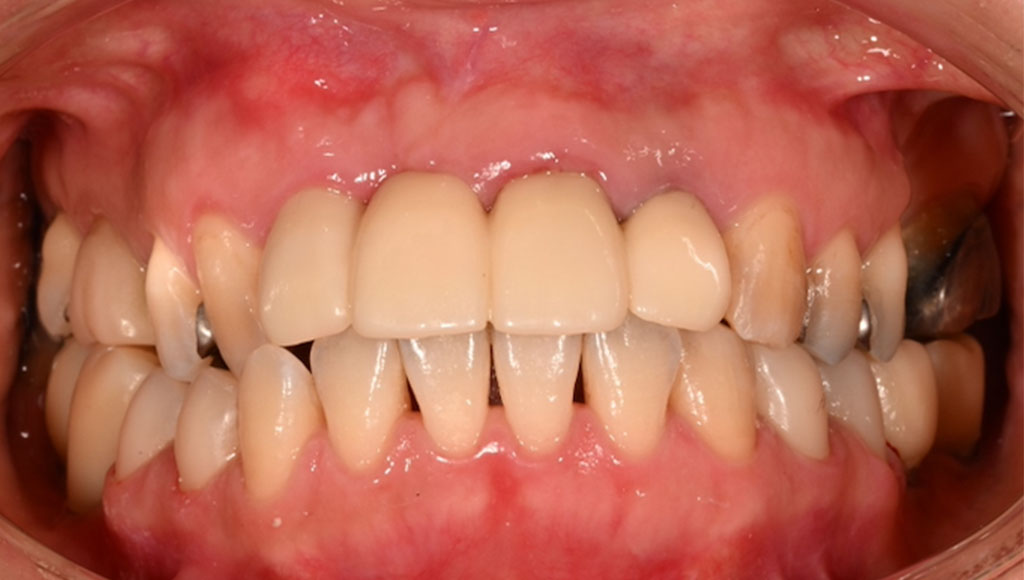

After1

患者様の主訴

50代女性。横浜市在住。左下45番、右下45番の奥歯の銀歯が見た目に気になりご来院。

診断結果

左下45番、右下45番のインレーを外し、歯の形成を行いジルコニアクラウンをセット

治療内容

ジルコニアクラウンを装着するために元のインレーを外し、歯の形成を行い光学印象(プライムスキャンによる)型取りを行いました。光学印象のデータを元に当院の院内技工室にてデジタル加工を行い、ジルコニアクラウンを作成し、セットを行いました。

治療期間

2回

治療費用

総額:440,000円(税込)

◼️内訳

ジルコニアクラウン:110,000円(税込)/1本×4本

光学印象(プライムスキャン)

リスク・副作用

補綴物の脱落・欠落、咬合違和感、色調補正